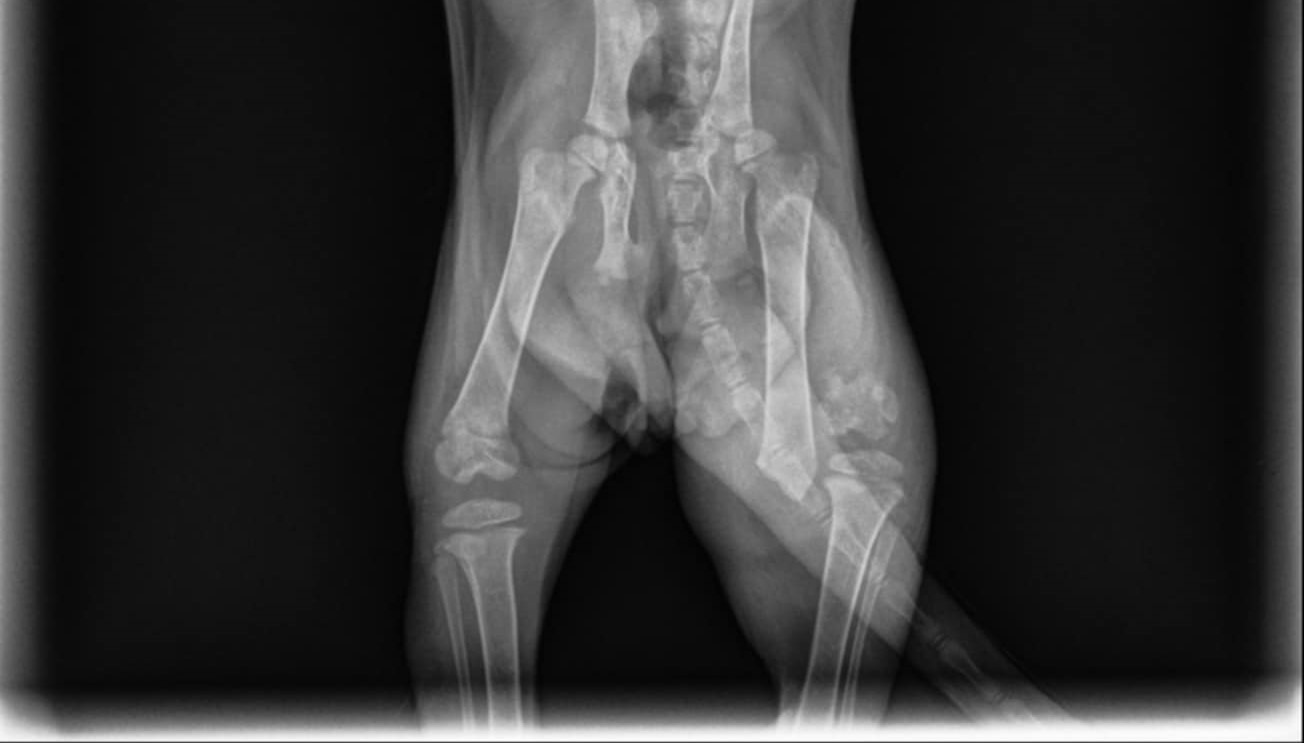

This is Luca! We rescued her along with her mother and two sisters 5 weeks ago, and estimate her to be roughly 8-9 weeks old now. We believe she was born Paraplegic, but is to young for an MRI to confirm. So she drags her legs behind her at all times which has also made her incontinent. She has been to the vet 4 times now leading to what is now going to be an amputation of her left back leg.

Now, this last week during our routine physical therapy to help improve her mobility, I realized I could not move and rotate her back left leg anymore. After a visit to the vet, it turns out she has broken her leg at the growth plate. The vet has recommended the amputation of her back left leg. After we heard this, we decided to keep her permanently to ensure she gets the best love and care she can.